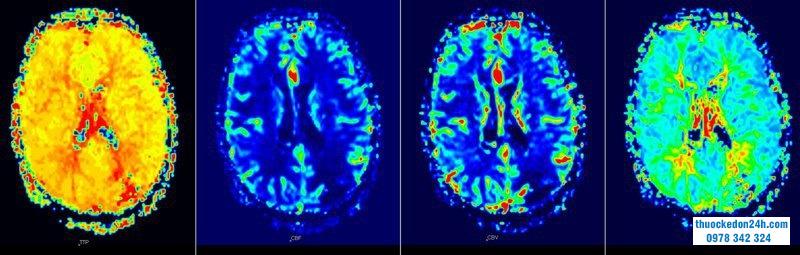

1.5.Chụp cắt lớp phát xạ positron

Chụp cắt lớp phát xạ positron 18F-fluorodeoxyglucose ( 18- F-FDG-PET) là một xét nghiệm chẩn đoán phản ánh tình trạng di truyền, phân tử, chuyển hóa và chức năng của tổn thương. Giá trị hấp thu tiêu chuẩn hóa tối đa (SUVmax) thu được bằng hình ảnh PET phản ánh sự chuyển hóa glucose của các khối u. Choi và cộng sự đã khám phá mối quan hệ giữa đáp ứng điều trị sớm sau xạ trị hóa chất bổ trợ tân sinh bằng FDG-PET và kết quả phẫu thuật trong ung thư biểu mô tuyến ống tụy tiên tiến tại chỗ.